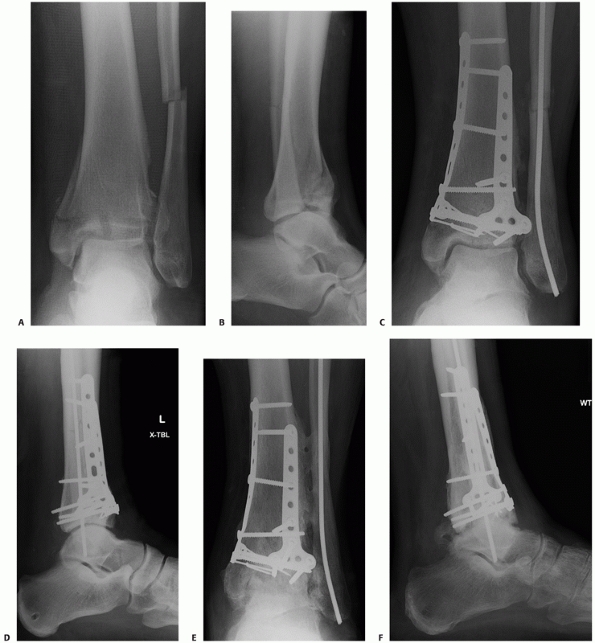

FIGURE 56-8 Anteroposterior (A) and lateral (B)

injury radiographs of a 42-year-old man after falling from a ladder. Initial displacement demonstrates varus angulation with anterior translation of the talus relative to the tibia. The associated transverse fibular fracture at the level of the tibial plafond indicates a tensile failure mechanism of the fibula. After fibular fixation and tibiotalar external fixation, the axial CT scan (C) demonstrates the three commonly identified major fragments: a medial malleolar fragment, an anterolateral (Chaput) fragment, and a posterior malleolar (Volkmann) fragment. Articular comminution is noted between all fracture fragments, most notably at the central intersection of all three fragments. |

Compressive fibular failure is commonly seen with tibial plafond

fractures that present with valgus angulation, whereas tension fibular

failure is commonly identified with tibial plafond fractures that

present with varus angulation (Fig. 56-8). The